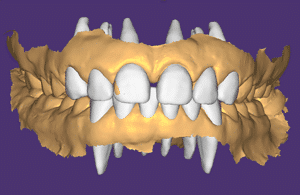

Les photographies et l’empreinte numériques sont envoyées au laboratoire (laboratoire LM2M, Paris 8e). Nous indiquons sur la fiche d’augmenter la DVO pour rétablir l’esthétique du sourire et de créer un wax-up virtuel des deux blocs incisivo-canins. Le laboratoire envoie un fichier 3D sur Exocad avec le wax-up virtuel (Fig.3a, b, c). Cette étape est très importante et permet au praticien de décider du plan de traitement.

Fig.3a, b, c : Le laboratoire envoie un fichier 3D sur Exocad avec le wax-up virtuel.

Fig.3b.

Fig.3c.

– Le décalage des milieux est plus prononcé et la fonction canine droite n’a pas pu être rétablie. Lorsqu’on ouvre artificiellement la DVO, la mâchoire inférieure recule (2). Ce recul est compensé par l’augmentation de volume palatin des incisives maxillaires et, éventuellement, par l’augmentation du volume vestibulaire des incisives mandibulaires. Ici, la malocclusion a été accentuée sans compensation prothétique possible. Sans orthodontie associée, la patiente doit être prévenue que le traitement sera un traitement de « compromis » au point de vue fonctionnel.

– Pour obtenir la longueur « idéale » du bloc IC maxillaire, la DVO a dû être augmentée de 4 mm en antérieur, ce qui correspond à environ 2 mm en postérieur (3). Il va falloir choisir comment répartir ces 2 mm (tout à la mandibule ? tout au maxillaire ? + 1 mm sur la mandibule et + 1 mm au maxillaire ?). C’est la première difficulté des plans de traitement dans les cas d’usure. Pour se décider, il faut regarder le bloc IC mandibulaire. Ici, pour rétablir l’esthétique et la courbe de Spee, on s’aperçoit qu’il faut beaucoup augmenter la hauteur des prémolaires mandibulaires et moins celle de 36 et 46. Ce qui nous arrange car la patiente présente des usures plus marquées sur 36, 35, 34, 44, 45, 46, 16 et 26. Il a donc été décidé de donner la quasi-totalité des 2 mm aux prémolaires mandibulaires et de répartir 1 mm/1 mm entre 16/46 et 26/36.

Selon la classification ACE de F. Vailati (4), les incisives maxillaires vont être restaurées en technique « sandwich » : composite en palatin et facette céramique en vestibulaire. Ici on a augmenté la DVO de 4 mm. En analysant le wax-up numérique, on s’aperçoit que les faces palatines ont été épaissies d’environ 2 mm (pour compenser le recul de la mandibule) et que le bloc IC mandibulaire a été allongé d’un peu moins de 2 mm (pour rétablir le guide antérieur le plus parfait possible). C’est là tout l’avantage du wax-up numérique : on peut faire varier les contrastes pour voir en superposition les dents initialement et les dents waxées. 2 mm est un chiffre-clé en dentisterie adhésive. Il correspond à l’épaisseur maximale de photopolymérisation d’un composite de restauration en technique directe. Voilà qui nous aide pour notre choix…